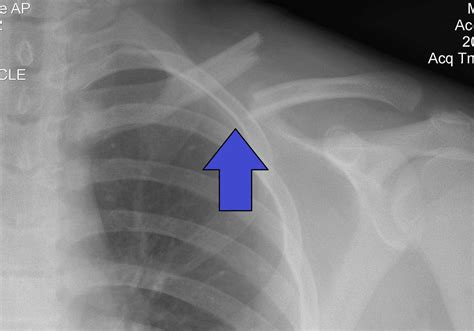

To confirm a clavicle fracture, a healthcare provider will perform a physical examination and order imaging tests. Common diagnostic tools include:

• X-rays: These provide clear images of the bone and can show the location and severity of the fracture.